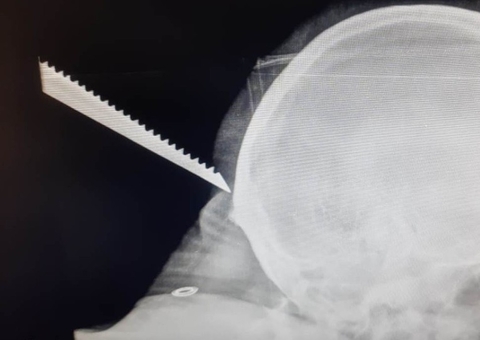

Segundo o The Sun, o homem alegou ter escorregado enquanto fazia uma limpeza e caído sobre o projétil que havia acabado de colocar no chão. Com o projétil de 17 cm de comprimento no reto do paciente, o hospital acionou uma equipe antibomba com medo de que pudesse haver uma explosão.

"Era um pedaço de chumbo pontudo e grosso, projetado para atravessar um tanque", disse um dos integrantes do 11º Regimento de Descarte de Artilharia Explosiva.